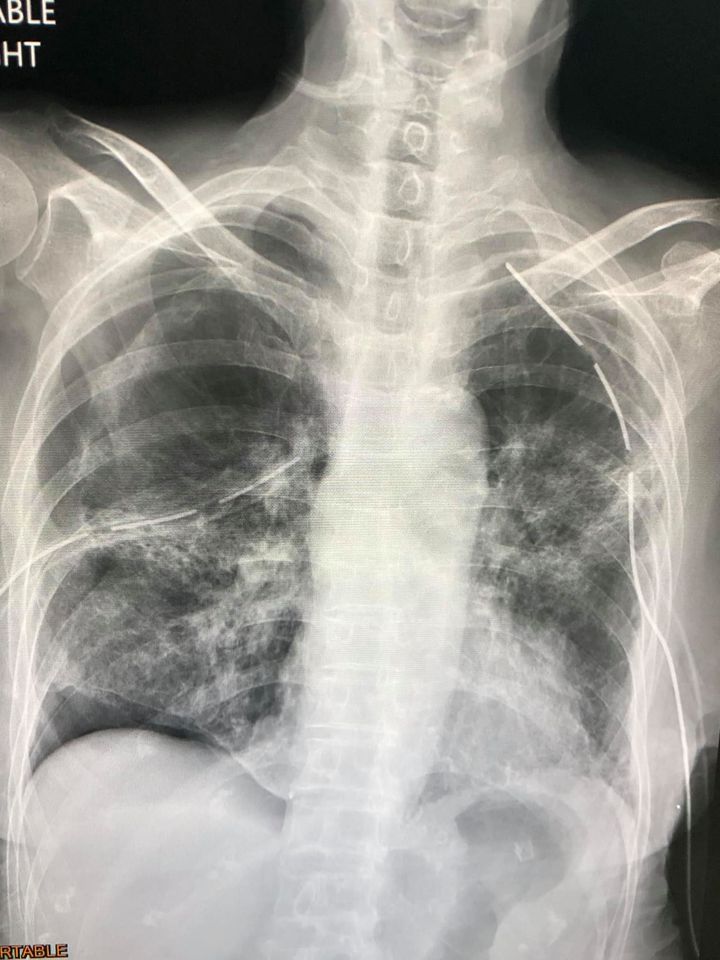

ล่าสุดพบผู้ป่วยไทยปอดรั่วเองทั้ง 2 ข้าง เป็นผลจากการที่เนื้อปอดถูกทำลายโดยเชื้อไวรัสโควิด-19 โดยเป็นผู้ป่วยหญิงไทยอายุ 77 ปี ไม่สูบบุหรี่ ปกติแข็งแรง ไม่มีปัญหาทางปอด ยังไม่ได้ฉีดวัคซีนป้องกันโรคโควิด

- วันที่ 8 กรกฎาคม มีไข้ ไอ เหนื่อย ปอดอักเสบทั้ง 2 ข้างจากโรคโควิด-19 ได้รับการรักษาด้วยยาและออกซิเจน ไม่ได้ใส่เครื่องช่วยหายใจ

- วันที่ 30 กรกฎาคม 22 วันหลังเริ่มป่วย มีอาการเหนื่อยมากขึ้นจากปอดข้างซ้ายรั่วเอง ต้องใส่ท่อระบายลม ถอดท่อระบายลมออก

- วันที่ 9 สิงหาคม ปอดอีกข้างรั่วเอง

- วันที่ 18 สิงหาคม ต้องใส่ท่อระบายลม

- วันที่ 23 สิงหาคม ปอดข้างซ้ายรั่วอีก ต้องใส่ท่อระบายลมอีกครั้ง

- วันที่ 28 สิงหาคม ถอดท่อระบายลมข้างซ้าย

- วันที่ 31 สิงหาคม ปอดข้างซ้ายรั่วอีก ต้องใส่ท่อระบายลมครั้งที่ 3

- วันที่ 2 กันยายน ทำคอมพิวเตอร์สแกนปอดพบพังผืดทั่วปอดร่วมกับหลอดลมเล็กๆโป่งพอง

- วันที่ 10 กันยายน ได้ทำการผ่าตัดปอดข้างขวาเพราะปอดขวาไม่ขยายตัวเต็มที่ ด้วยการส่องกล้องเข้าไปในช่องทรวงอกข้างขวา พบถุงลมพองโตที่ผิวของยอดปอดข้างขวาด้านบนและด้านล่าง ต้องตัดปอดเฉพาะส่วนนั้นและเย็บปิด ตัดเยื่อหุ้มปอดด้านขวา ใส่แป้งทัลค์ เข้าช่องปอดขวา และผ่านท่อระบายลมข้างซ้าย เพื่อให้เยื่อหุ้มปอดข้างขวาและซ้ายติดกัน

และส่งชิ้นเนื้อปอดตรวจทางพยาธิวิทยา พบว่า เนื้อปอดถูกทำลาย มีทั้งอักเสบและพังผืดทั่วไป มีถุงลมพองในเนื้อปอด ขณะนี้ยังต้องใส่ท่อระบายลมทั้งสองข้าง